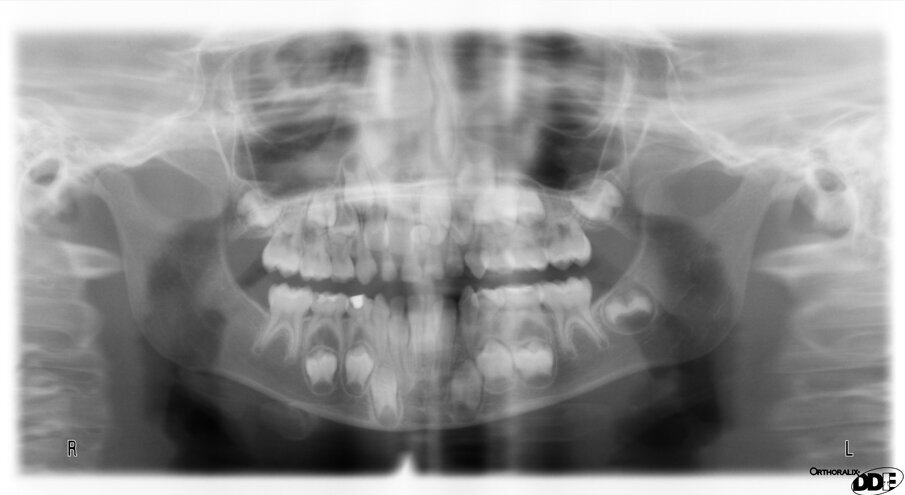

An eight and half year-old girl (LT) attended the paediatric dentistry department of Hamdan Bin Mohammed College of Dental Medicine (HBMCDM) in Dubai Healthcare City for an opinion. The patient’s mother was concerned about the delayed eruption of an upper front tooth (21) that was affecting her child’s appearance (Figs. 1 a, b & c). LT was medically fit and healthy with no history of previous dental trauma. She was in the mixed dentition stage. Tooth 11 had erupted 4 months ago in cross bite but 21 had not erupted yet. Its eruption was much delayed (usually erupts at 7 ½ years of age). Looking back at previous x-rays, a DPT was taken a year ago and it was noticed that an important feature was missed. Retrospectively, the presence of a supernumerary tooth ($) in the area of 21 and congenital missing 47 was confirmed (Fig. 2). Two new x-rays, namely upper intra oral periapicals and the parallax technique (distal shift) showed a supernumerary tooth (conical and inverted) in a palatal position (Figs. 3 a & b). LT also had dental caries of her primary teeth (Figs. 4 a & b), had a pronounced gag reflex and was dentally anxious.

Fig. 2. A previously taken DPT of 8 ½ year old (LT) when she was 7 showed the presence of a supernumerary tooth ($) (arrow) in the maxillary midline. This was accidently omitted at the time indicating the importance of a comprehensive report every time an x-ray is taken.

Figs. 3 (a & b). Periapical xrays show the presence of an inverted conical supernumerary tooth present palatally to 21 (parallax).